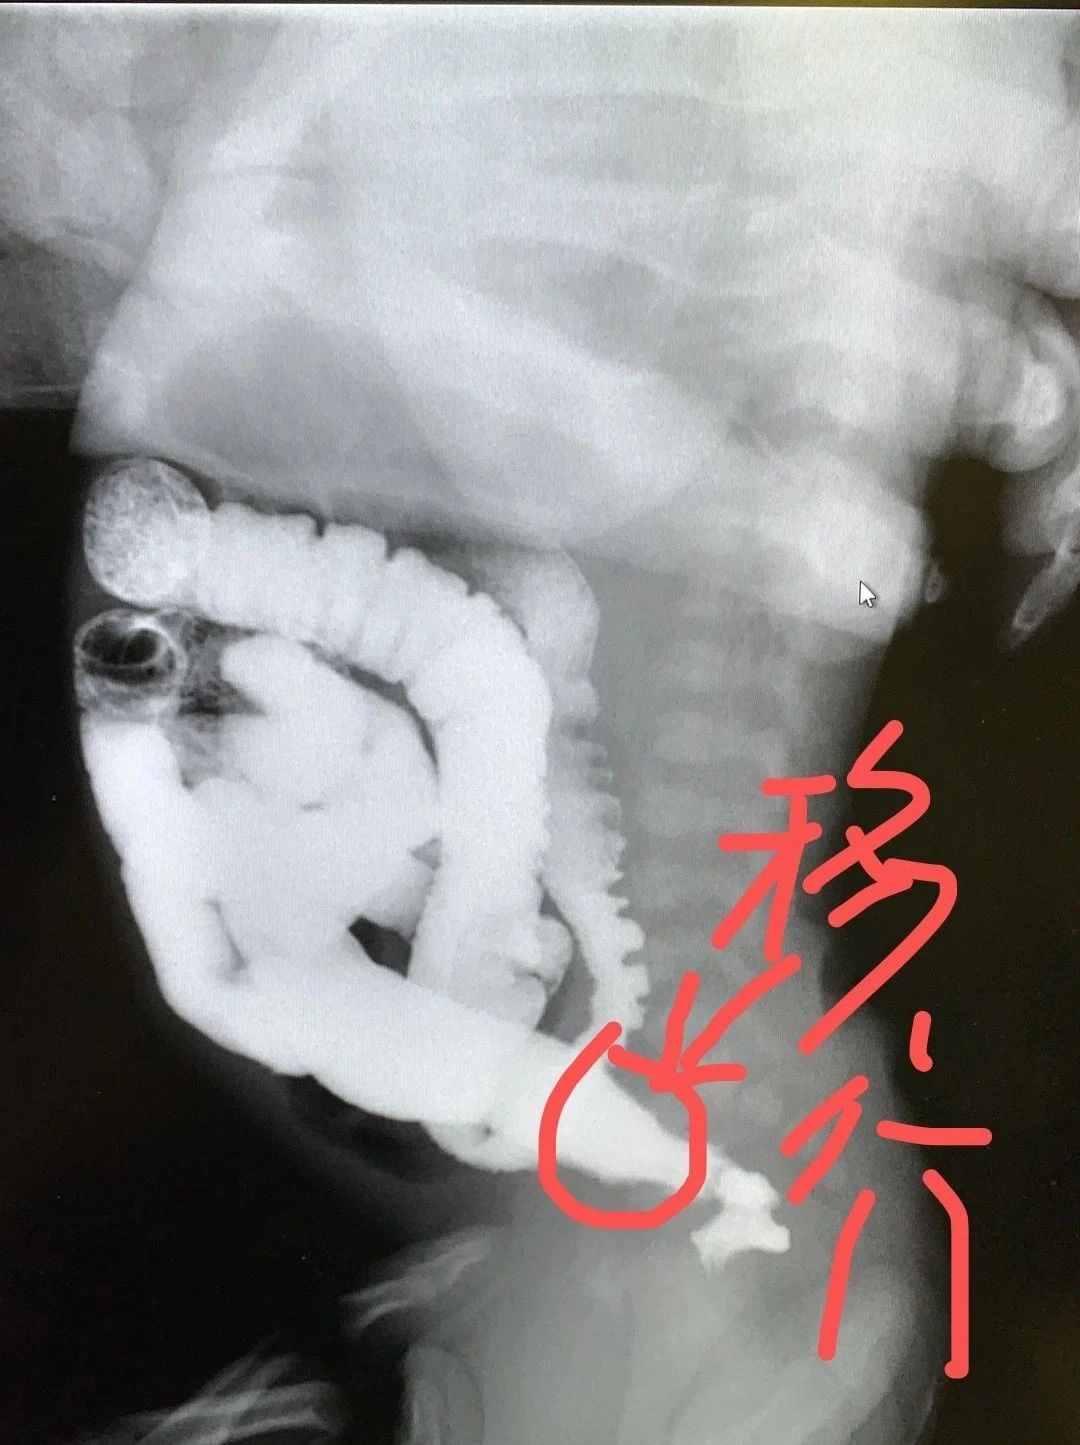

孩子甲状腺功能等血液检测是正常的。但是,下消化道钡剂灌肠结果不正常,下面圈内上宽下窄,漏斗样移行。提示:先天性巨结肠可能。

钡剂灌肠:对先天性巨结肠,钡剂灌肠可以发现远端狭窄的肠段与近端扩张的肠段。狭窄最常见的部位是直肠与乙状结肠远端。